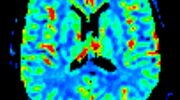

• Diffusionswichtung

• Perfusionswichtung

• Suszeptibilitätswichtung